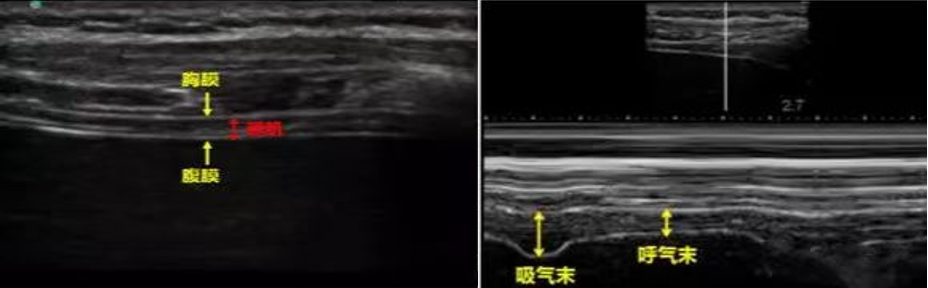

2. 膈肌的厚度及变化率

模式:M超,采样线垂直于膈肌,测量吸气末和呼气末的膈肌厚度。探头:线阵。部位:左、右侧腋前线7~9肋间,探头沿着肋间隙;左、右腋中线7~8肋间,探头标志朝向头侧。

图片

图16  膈肌超声

增厚率%=(吸气末厚度-呼气末厚度)/吸气末厚度×100%,同样至少测量3次呼吸周期求得平均值。